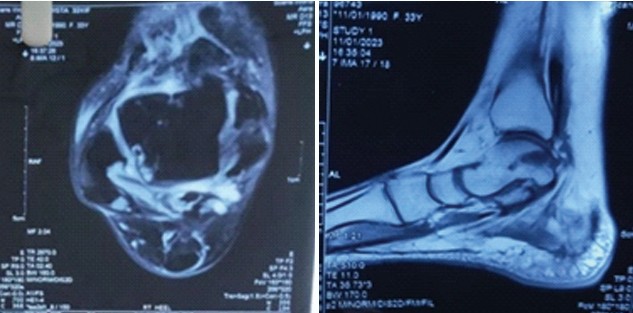

The anterior or posterior two-portal approach is selected based on the location of the osteochondral lesion of the talus (OLT). Patients undergoing the anterior approach were positioned supine position. An anteromedial and anterolateral two-portal approach was made (Fig. 1 and 2). Just medial to the tibialis anterior tendon helps define the anteromedial portal and the anterolateral portal just laterals to the peroneus tertius tendon. Arthroscopic microfracture is a reparative cartilage procedure performed under direct visualization to address OLTs (Fig. 3). For reference, Figure 4 shows osteochondral lesion over the talus.

Figure 3: Arthroscopic view of microfracture.

Figure 4: The above images show osteochondral lesion over the talus.